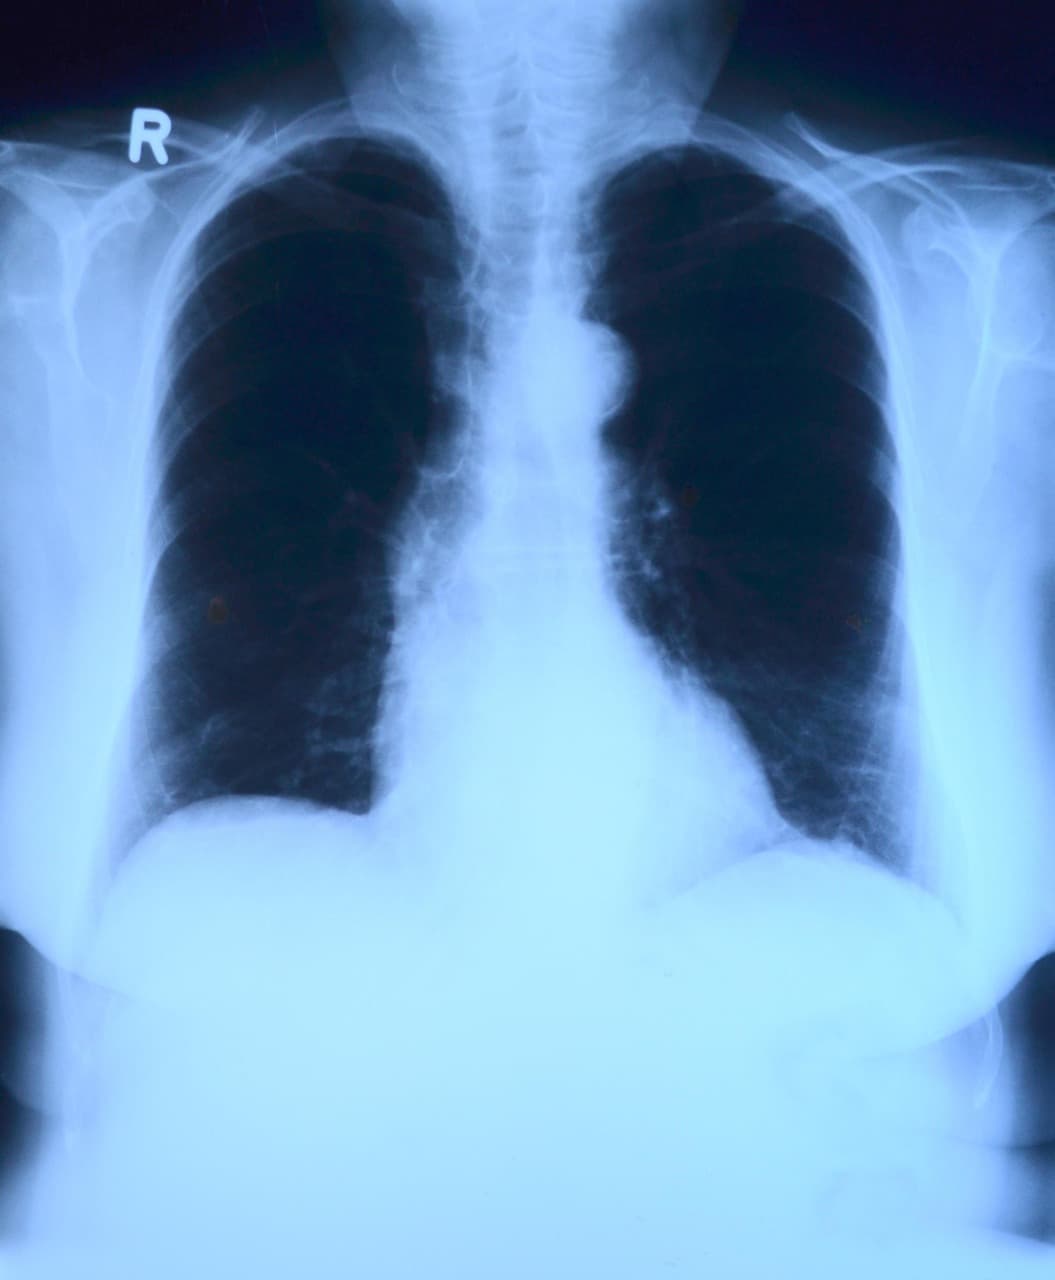

폐암 진단 과정에서 가장 기본이고 흔히 시행되는 영상 검사는 **흉부 X선 사진(chest X-ray)**이다. 병원에 처음 내원했을 때 기침, 객혈, 숨참 등 폐 관련 증상이 있을 경우, 의사는 보통 간단한 흉부 X선을 먼저 찍는 경우가 많다. X선은 비교적 비용이 낮고 검사 시간이 짧으며, 폐·늑골·기관의 해부학적 구조를 빠르게 확인할 수 있다는 장점이 있다. ([turn0search2]) 그러나 X선 영상은 해상도가 낮고, 특히 작은 폐 결절이나 조기 병변을 놓치기가 쉽다는 한계가 있다. 실제로 X선 검사만으로는 종양이 상당히 커지거나 진행된 경우에야 명확하게 보이는 경우가 많고, 조기 폐암은 그림자(shadow)로만 나타날 수 있어 진단이 어려운 경우가 많다. ([turn0news14])

게다가 X선만으로는 악성(암)과 양성 병변을 구별하는 데 한계가 크다. 뼈, 혈관, 다른 조직이 겹쳐 보이면서 종양이 있는 부위가 잘 숨겨지거나 혼동될 수 있다. ([turn0search2]) 따라서 흉부 X선에서 이상 음영이 발견되면, 보통 이를 근거로 더 정밀한 영상 검사(예: CT)를 추가로 시행하게 된다. 이처럼 흉부 X선은 초기 스크리닝 도구로는 유용하지만, 폐암 확진이나 병기 결정을 위한 결정적 도구로는 불충분할 수 있다.